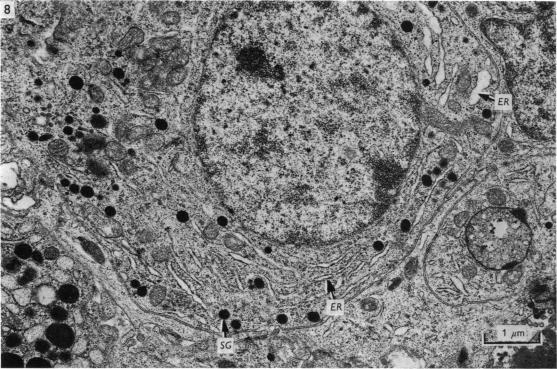

关于草原毛丝鼠(Lagostomus maximus)腺垂体超微结构的一些观察。

Some observations on the ultrastructure of the adenohypophysis of the Plains viscacha (Lagostomus maximus).

The ultrastructural appearance of the pars distalis of the Plains viscacha is described. Of particular interest are the prolactin cells and stellate cells and the intercellular cysts or channels which may be part of a transport system for hormones.

摘要